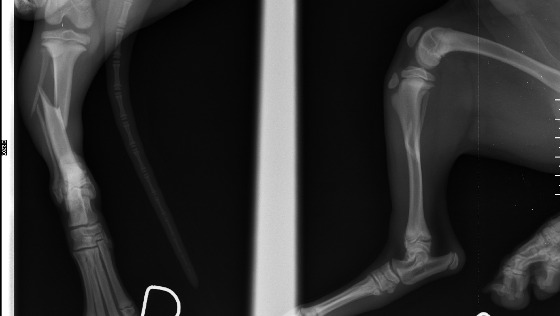

Chcielibyśmy Państwu serdecznie podziękować za wsparcie Gringo! Łapka ładnie się zagoiła, a o opatrunku gipsowym psiak już dawno zapomniał bo biega na spacerach jak sarenka :). To dzięki Państwu udało nam się pokryć koszty leczenia. To dzięki Państwu jesteśmy w stanie pomagać bezdomnych zwierzakom, leczyć je i szukać im kochającego domku. Z całego serca Państwu dziękujemy!